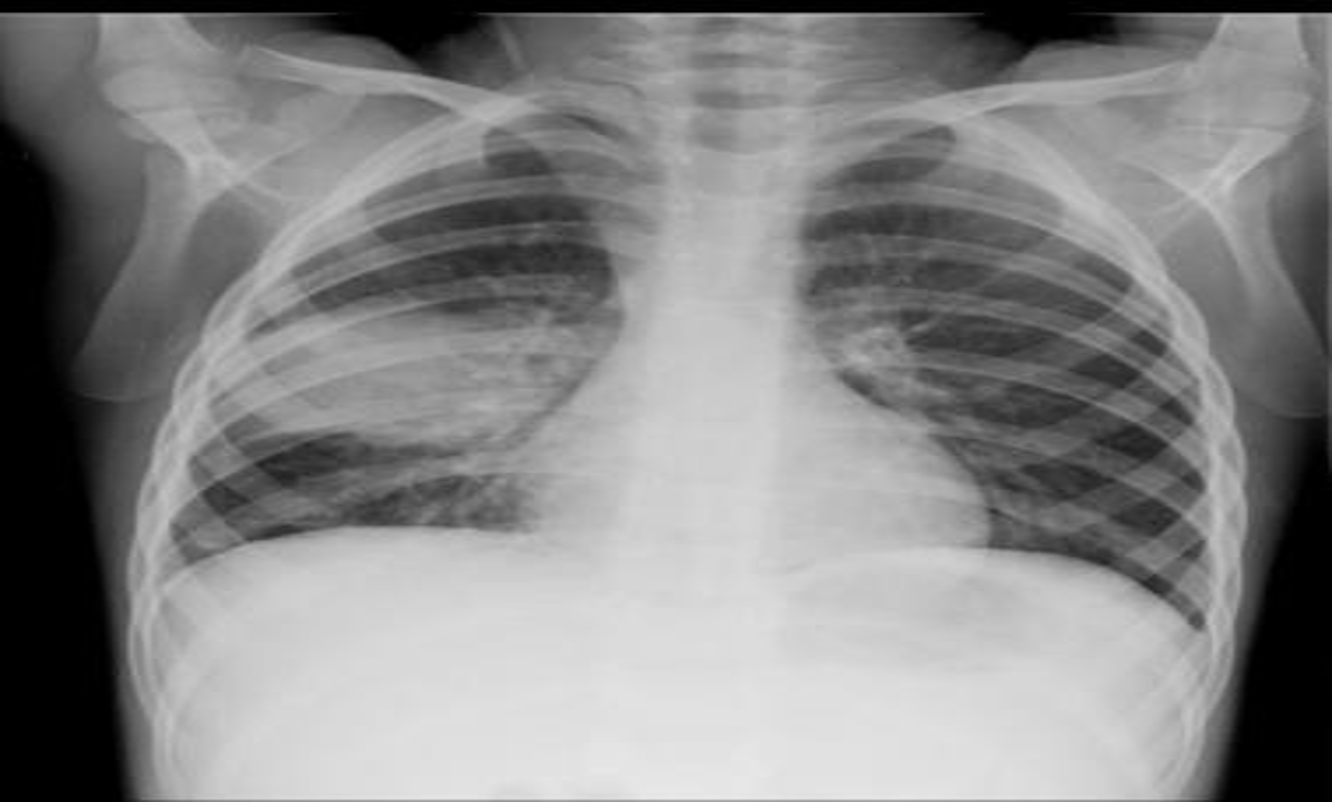

Chest X-Ray showing patch of pneumonia

Image of chest x-ray displaying the interstitial pattern seen in viral pneumonia. The interstitial pattern shows fine lines radiating from the hila.

These chest X rays compare clear, healthy lungs with the cloudy, inflamed lung tissue of pneumonia.

Right lower lobe consolidation in a patient with bacterial pneumonia.